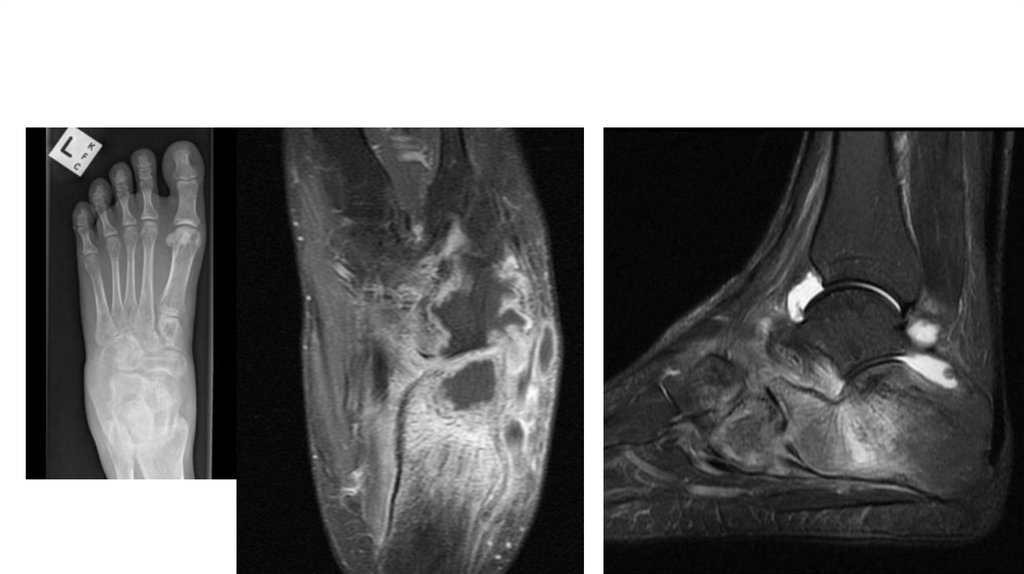

Воспалительные заболевания опорнодвигательного аппарата

«Воспалительные

заболевания опорнодвигательного аппарата»